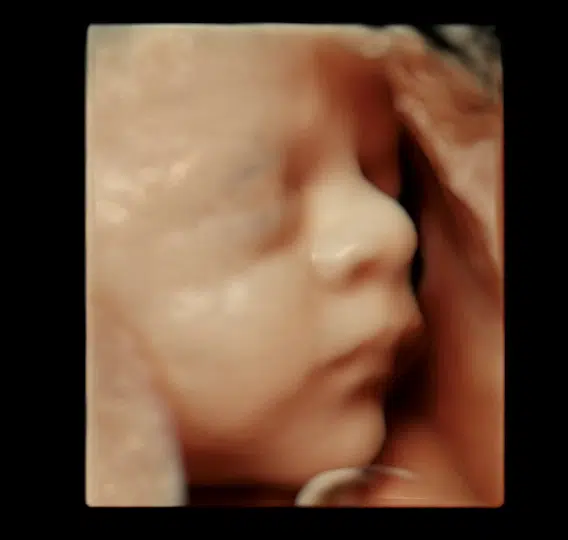

- I 3D ser du barnet, som det rigtigt ser ud inde i maven: Man kan se ansigtstræk, fingre, tæer og navlesnor. Sætter man 4D til, så filmer man og får bevægelser med.

En 3D-scanning giver dig mulighed for at komme endnu tættere på dit barn og opleve de små detaljer, der gør netop jeres barn unikt. Med naturlig 3D og HDlive får du billeder, som giver et livagtigt indtryk – næsten som at se dit barn i virkeligheden.

Når vi tilføjer den fjerde dimension (4D), bliver oplevelsen endnu mere levende, fordi du kan se dit barn bevæge sig. Ligger barnet godt, kan du måske opleve et smil, et gab, en lille hånd i munden eller andre personlige bevægelser.